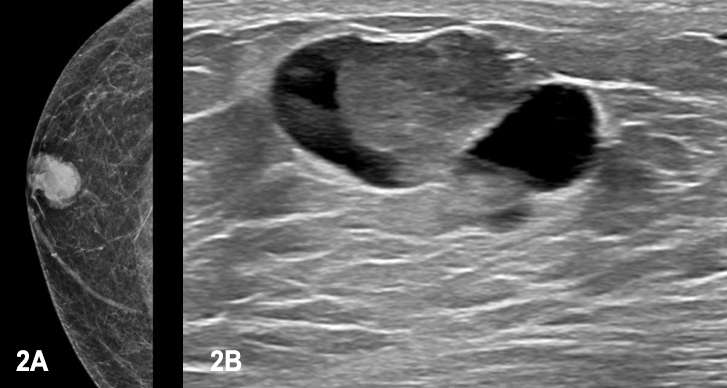

No definite sonographic or mammographic features can be used to reliably distinguish the different subtypes of papillary carcinoma. Mammographically, they often present as large, well defined, lobulated masses. On ultrasound, they are usually hypoechoic, solid and cystic masses with or without associated posterior acoustic enhancement.6 On MRI, they usually present as enhancing complex cystic or multicystic lesions with a solid central component; the solid component can show either homogeneous or heterogeneous enhancement. 7

Case 2